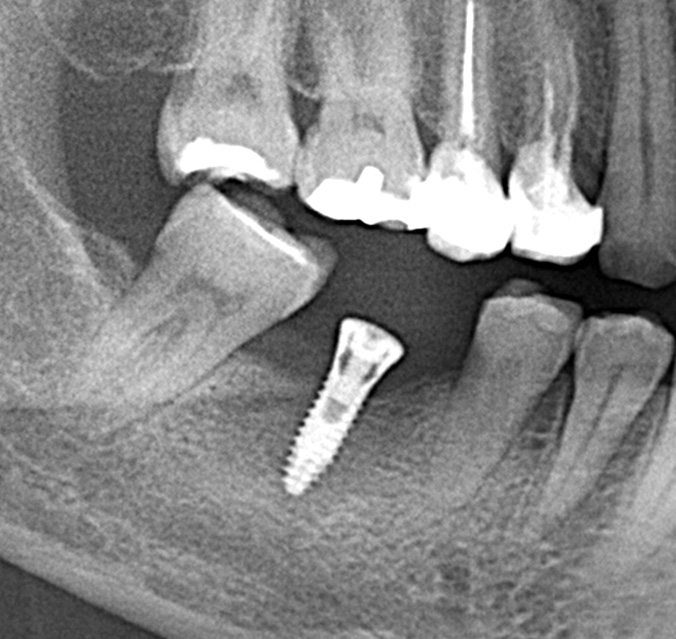

パノラマレントゲン写真 -

親抜歯後、歯ぐきは治癒しました。しかし、インプラント治療のためには骨が不足していました。

インプラント手術を行いました。

レントゲン画像 -